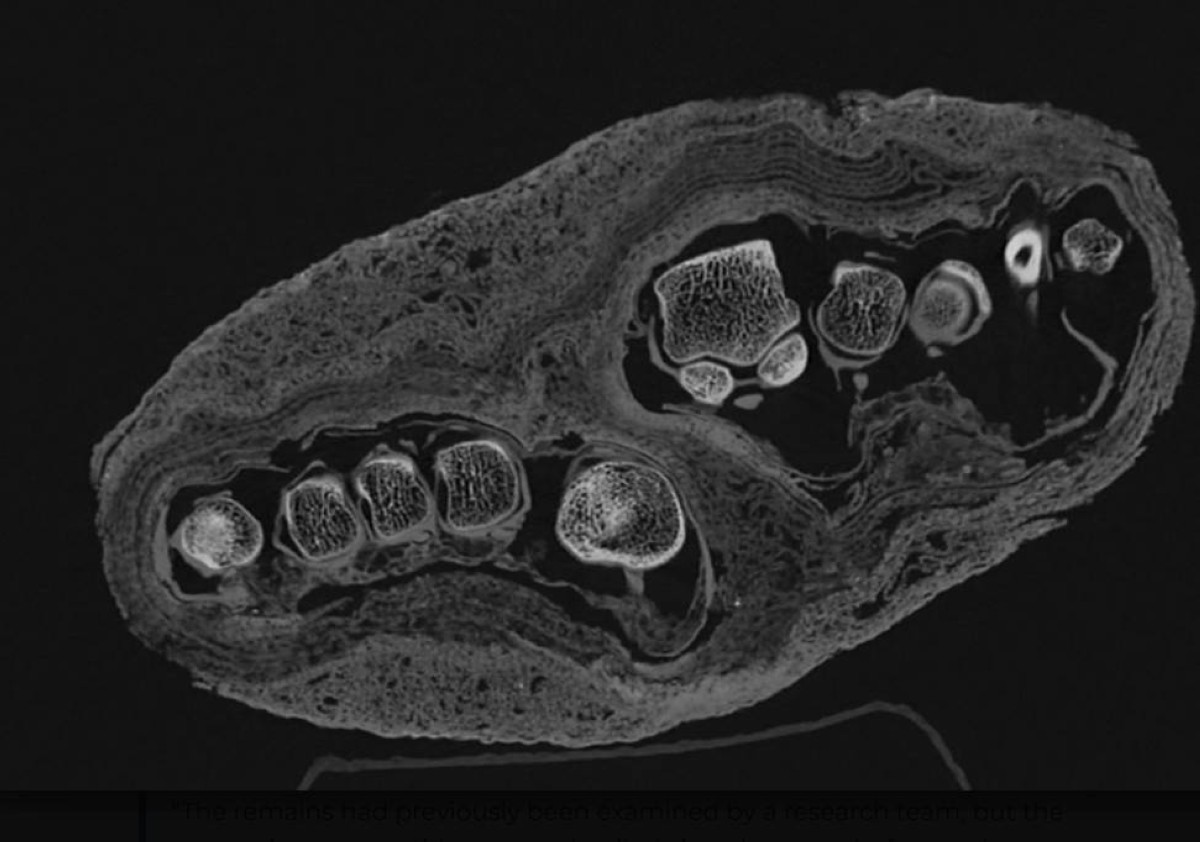

في الماضي، كانت دراسة المومياوات تتطلب في كثير من الأحيان فتح لفائف الكتان، ما يؤدي إلى تلف أجزاء من الجثة أو فقدان معلومات مهمة. أما اليوم، فقد أصبح بإمكان الباحثين استخدام تقنيات متطورة مثل التصوير المقطعي المحوسب (CT)، التي تعتمد على الأشعة السينية والحوسبة لإنتاج صور ثلاثية الأبعاد دقيقة لما يوجد داخل الجسم، طبقة تلو الأخرى، دون أي تدخل جراحي.

توضح إيبوليكا دوداس، أخصائية الأشعة المشاركة في المشروع، أن الهدف من هذه الفحوصات هو بناء صورة دقيقة للبنية الداخلية للمومياوات، بما يشمل العظام والأنسجة وأي تشوهات أو أمراض محتملة، كما تساعد هذه التقنية في فهم الأساليب التي استخدمها المصريون القدماء في التحنيط، والتي تطورت على مدار قرون طويلة وفق semmelweis.

وقد أظهرت الفحوصات الأولية لبعض المومياوات في المتحف نتائج مثيرة للاهتمام، فعلى سبيل المثال، تم تحديد عمر عدد من العينات باستخدام تقنية الكربون المشع، حيث يعود تاريخ أقدمها إلى ما بين القرن الخامس والثالث قبل الميلاد، كما كشفت الصور عن اختلافات في تقنيات التحنيط، ما قد يساعد في تحديد الفترة الزمنية التي تعود إليها كل مومياء.

ومن أبرز الاكتشافات التي حققها الفريق، حل لغز حزمة محنطة كان من الصعب تحديد محتواها من الخارج. في البداية، اعتقد الباحثون أنها قد تحتوي على طائر، نظراً لانتشار عادة تحنيط الحيوانات في مصر القديمة، أو ربما رأس إنسان. لكن الفحوصات كشفت مفاجأة غير متوقعة: كانت الحزمة في الواقع تحتوي على قدم بشرية.